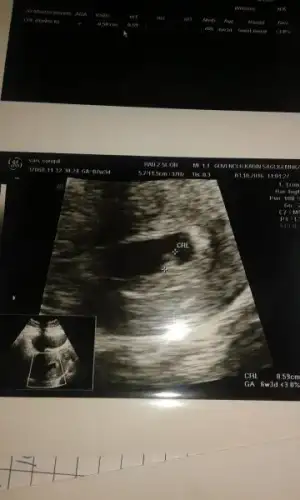

Kac haftalikti bu foto.? 13. Haftada soyluyorlar cinsiyeti. Hade inşallah kizina bi erkek kardeş gelir ... Rabbim kiz nasip etmis inşallah oglanida nasip eder . Zira her iki nimette tarifsiz :)